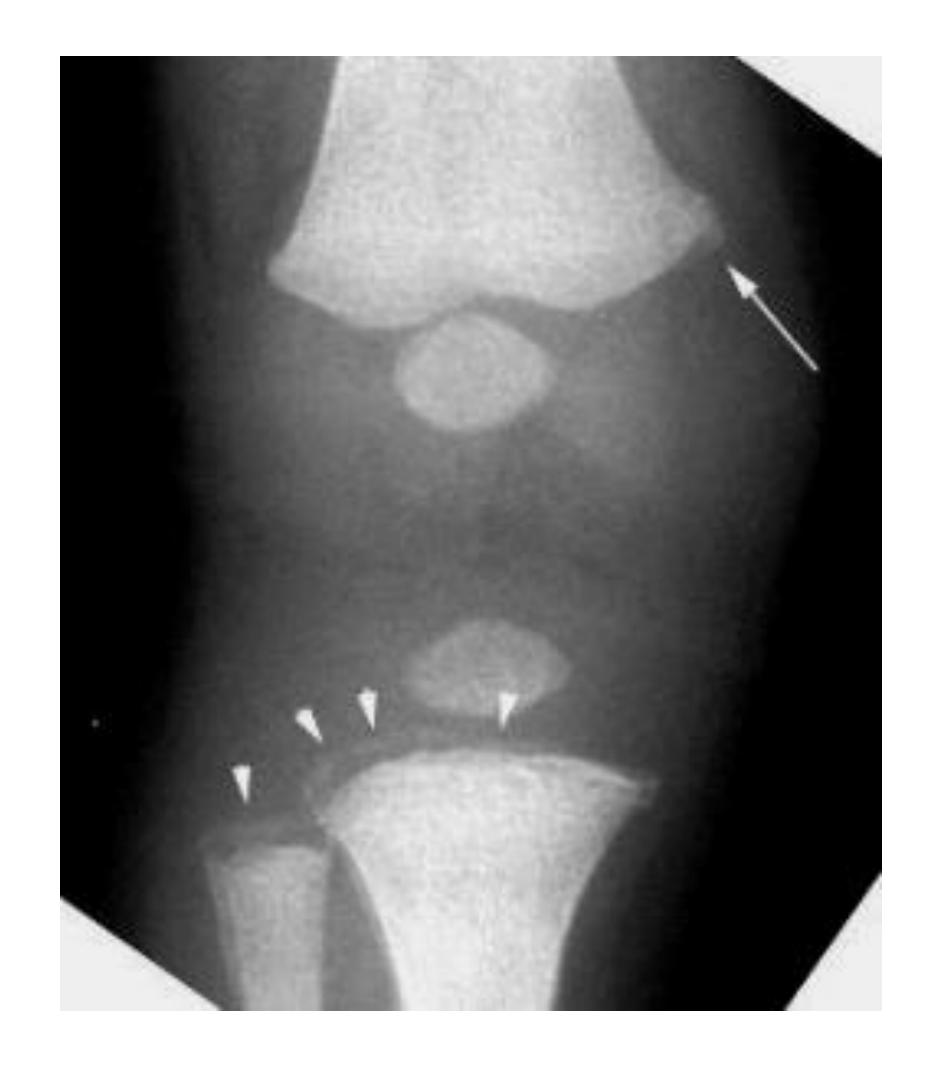

A teenager with acute onset of pain in the right hip during a run. He sustained the injury seen in the x-rays with a white arrow. This injury usually occurs due to a forceful eccentric contraction of which of the following muscles?

- C. Rectus femoris

- Sartorius

Which of the following muscles is attached to the structure pointed by the arrow?

- C. Sartorius

Note: Arrow was pointing at ASIS (Anterior Superior Iliac Spine)